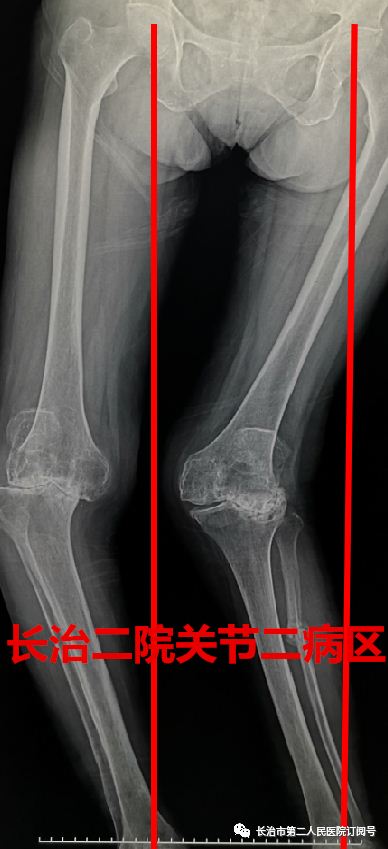

走路 在常人来看 是件多么轻松的事情 可对于李老太来说 近日,长治二院骨科关节二病区来了一位严重类风湿性关节炎患者,疾病困扰了她13年,日常行走已经很困难了。 长治二院骨科关节二病区 雷晓宇医师团队妙手回春 完美实施双膝关节置换术 随即轻松行走! 对李老太来说 走路成为了一种享受 今年69岁的李老太在13年前双膝先后出现疼痛无力的症状,但随着年龄的增长病情逐年加重,双腿关节等处都严重变形。双膝并拢时成“顺风腿”畸形,行走也变得相当困难,行各种保守治疗方案效果差,双膝疼痛行走受限,严重影响了日常生活。 图为:术前MRI及CT 图为:术后X片 据李老太的主管医生朱彦伟副主任医师介绍“重度外翻性膝行膝关节置换,由于其软组织不平衡及存在严重的骨缺损,手术难度极高,对于关节外科医师而言,绝对是充满挑战性事件! 入院后,骨科关节二病区雷晓宇医师团队术前进行仔细的手术规划,充分的术前准备,为李老太制定个性化治疗方案,对存在不同严重畸形的双膝分别行人工膝关节表面置换术。术后第二天就可以在助行器的保护下下床行走。经过精心的康复治疗,目前李老太的行走步态正常,生活质量明显提高。科室医护人员对李老太住院期间的精心治疗和护理,更是让老人及家属感受到了长治二院医护团队的专业素养和暖心服务。 对于像李老太这样的类风湿性关节炎患者,长治二院骨科关节二病区雷晓宇主任特别提醒:一旦出现疼痛、关节畸形、保守治疗无效后,应尽早行膝关节置换。 朱彦伟 关节二病区副主任医师 朱彦伟医师:周四全天门诊 电话:158 3551 0903 ■ 直通大医院丨9月18日长治二院关节外科一病区主任张鹏为您讲解《股骨头坏死的预防与诊治》 ■ 皮肤病患者的福音——又一“名医工作室”落户长治二院!!! ■ 长治二院特邀北京大学第一医院皮肤科教授陈喜雪来院指导讲学 供 稿丨朱彦伟 视 频 | 朱彦伟 编 辑丨张静晗 审 核丨雷 赫